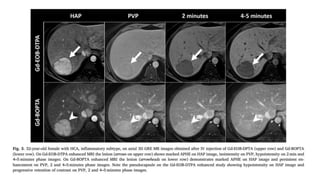

• Classic HCC …CT or MR imaging is a mass that shows

1. APHE

2. subsequent washout during PVP or more delayed images,

and

3. delayed capsular or pseudocapsular enhancement

• When present, these 3 major features allow HCC to be

treated without the need for biopsy confirmation

• Tumor thrombus may show arterial phase enhancement

• CT sensitivity 67.5% Specificity 92.5%

• MRI sensitivity 80.6% and specificity 84.8%